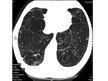

4. Krūšu kurvja Rtg-gr. Datortomogrāfija (g.k. emfizēmas diagnostikai).